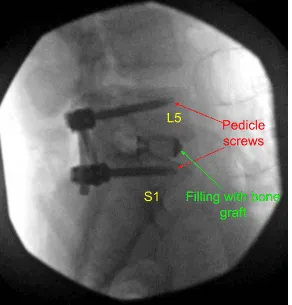

Then 40 mm x 6 mm of pedicle screws (Depuy Synthes) were inserted on either pedicle of S1 and checked under fluoroscopy and found to be in satisfactory position. Similarly, a pilot hole was made with the use of drill on either side of the pedicle of L5 followed by a gearshift to find the path under fluoroscopy. A ball-tipped probe was again used and all the walls were found to be intact. Again, tapping was done and 6 mm x 45 mm pedicle screws were inserted in either pedicle.

A trial cage was inserted and checked under fluoroscopy and it was decided to put a 9 mm x 36 mm titanium cage. Allograft was used and mixed with morselized auto bone graft of the lamina and spinous process. The cage and disc interspace was filled with bone graft and the cage was inserted and checked under fluoroscopy, found to be in satisfactory position.

Postoperative X Ray showed there is a normal lumbar lordosis. There were no destructive abnormalities or fractures. The intervertebral disc spaces appear preserved. There was no spondylolisthesis. The facet joints appear unremarkable.